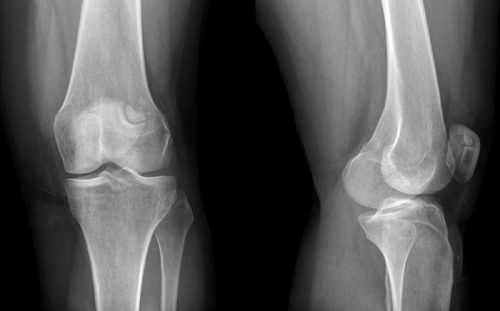

Насколько информативен рентген коленного сустава

В случае с коленом это обследование назначают при любых повреждениях и травмах, болезненности в покое и движении. Среди других показаний – припухлость, изменение цвета кожи, деформации и ограничение подвижности, симптомы, которые часто сопровождают артроз.

Самую большую диагностическую ценность рентген колена имеет при травмах – трещинах костей, переломах, вывихах и подвывихах суставов. Он диагностирует переломы мыщелков, травмы менисков и надколенника, кровоизлияния в коленный сустав. Метод позволяет обследовать сустав и прилегающие области – малоберцовую, бедренную и большеберцовую кости. С его помощью можно выявить артроз, артрит и остеопороз, а затем продолжить обследование другими методами.